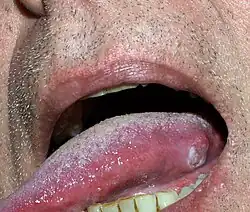

Plattenepithelkarzinome kommen vorwiegend in Körperregionen vor, die natürlicherweise von Plattenepithel bedeckt sind. Dazu gehören die äußere Haut und mechanisch stärker beanspruchte Schleimhäute wie Mundhöhle, Rachen, Stimmlippen, Speiseröhre, Vagina, Gebärmutterhals und Analregion. Weiterhin können Plattenepithelkarzinome über die Plattenepithelmetaplasie auch an anderen Stellen auftreten, z. B. in der Lunge.

Plattenepithelkarzinome wachsen warzenartig (verrukös) oder ulzerierend und ahmen das verhornende oder nicht-verhornende Plattenepithel in unterschiedlichem Umfang nach. Typisch für sie ist ein Zytoskelett aus Zytokeratin (CK). Hochdifferenzierte Karzinome dieser Entität verhornen und bilden, da die Hornschuppen im Tumorinneren liegen und nicht abgeschilfert werden können, zwiebelschalenartig geschichtete Hornkugeln (Hornperlen), die mikroskopisch meist eindeutig diagnostizierbar sind. Gering differenzierte Karzinome verlieren die Fähigkeit zur Hornbildung. Sie bilden sehr polymorphe (vielformige), solide Tumoren. Sehr stark entdifferenzierte (anaplastische) Plattenepithelkarzinome können in der spindelzelligen (fusiformen) Variante wie Sarkome aussehen.